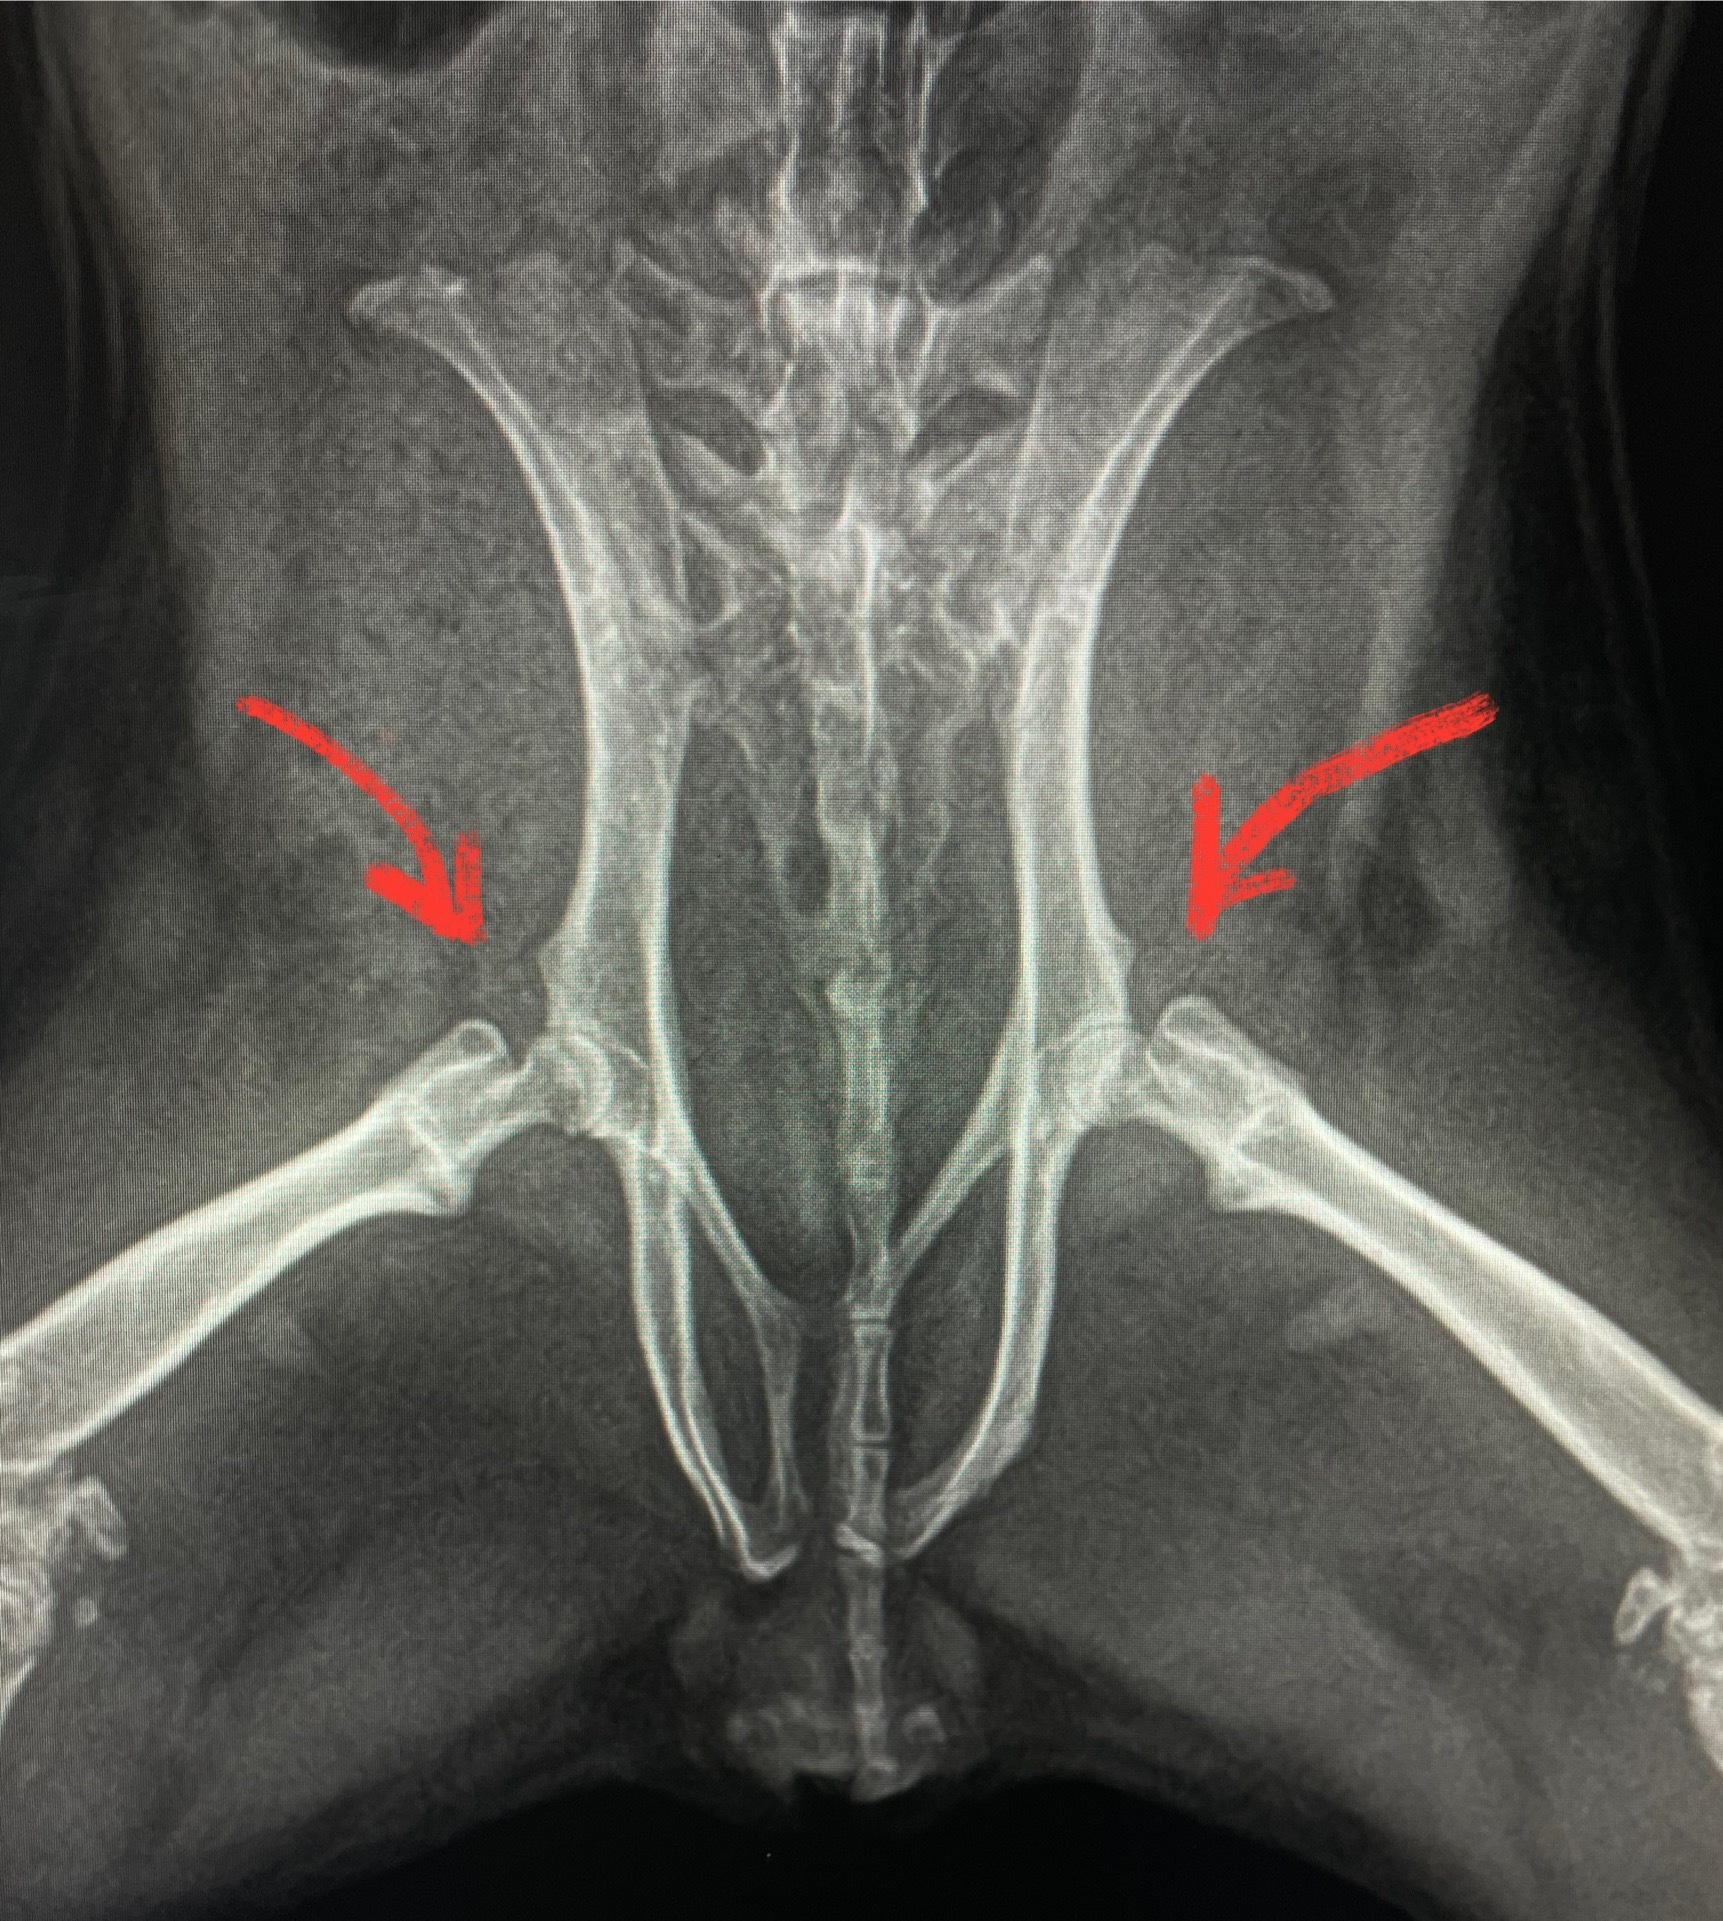

Делаю снимки в разных проекциях. Смотрю внимательно позвоночник, сами лапки – нормально. И тут добираюсь до тазобедренных суставов. Реакция одна: ой ой ой… Даже не смотря на возраст, выглядит плохо.

Что именно я увидела на рентгене: головки бедренной кости нормально в ямке таза не стоят, все «погрызанные» кривые и шейки тонкие.

Выглядело это всё настолько плохо, что мы с хозяином сразу обговорили вариант ампутации обеих тазовых конечностей при отсутствии положительной динамики на лечение (это вместе с обсуждением случая со старшим коллегой хирургом). Конечно, хозяин расстроился. Но что уж поделать. Такой у него ребёнок.

На лечении свинка начала ходить. Но главным звеном в принятии окончательного решения был рентген. Потому что если по нему нет улучшений, то большая вероятность, что могут начать разрушаться кости таза. И то, что свинка ходит снова – вообще не на пользу.